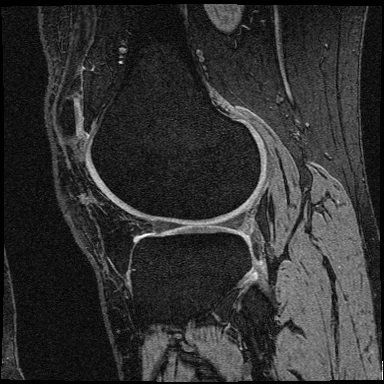

Data. The application of the COBRA score to the quantification of knee-osteoarthritis (OA) severity was carried out using the publicly available OAI-ZIB dataset ambellan2019automated . This dataset provides 3D MRI scans of 101 healthy right knees and 378 right knees affected by knee osteoarthritis, a long-term degenerative joint condition. Each knee is labeled with the corresponding Kellgren-Lawrence (KL) grade kohn2016classifications , retrieved from the NIH Osteoarthritis Initiative collection eckstein2012recent . The KL grade quantifies OA severity on a scale from 0 (healthy) to 4 (severe), as illustrated in Figure 7. Each voxel in the MRI scans is labeled to indicate the corresponding tissue (tibia bone, tibia cartilage, femur bone, femur cartilage or background).

Tables 3 and 4 provide a detailed description of the rehabilitation activities carried out by the subjects in the dataset used for quantification of stroke-induced impairment. Figure 7 shows examples of the MRI scans used for quantification of knee-osteoarthritis severity.